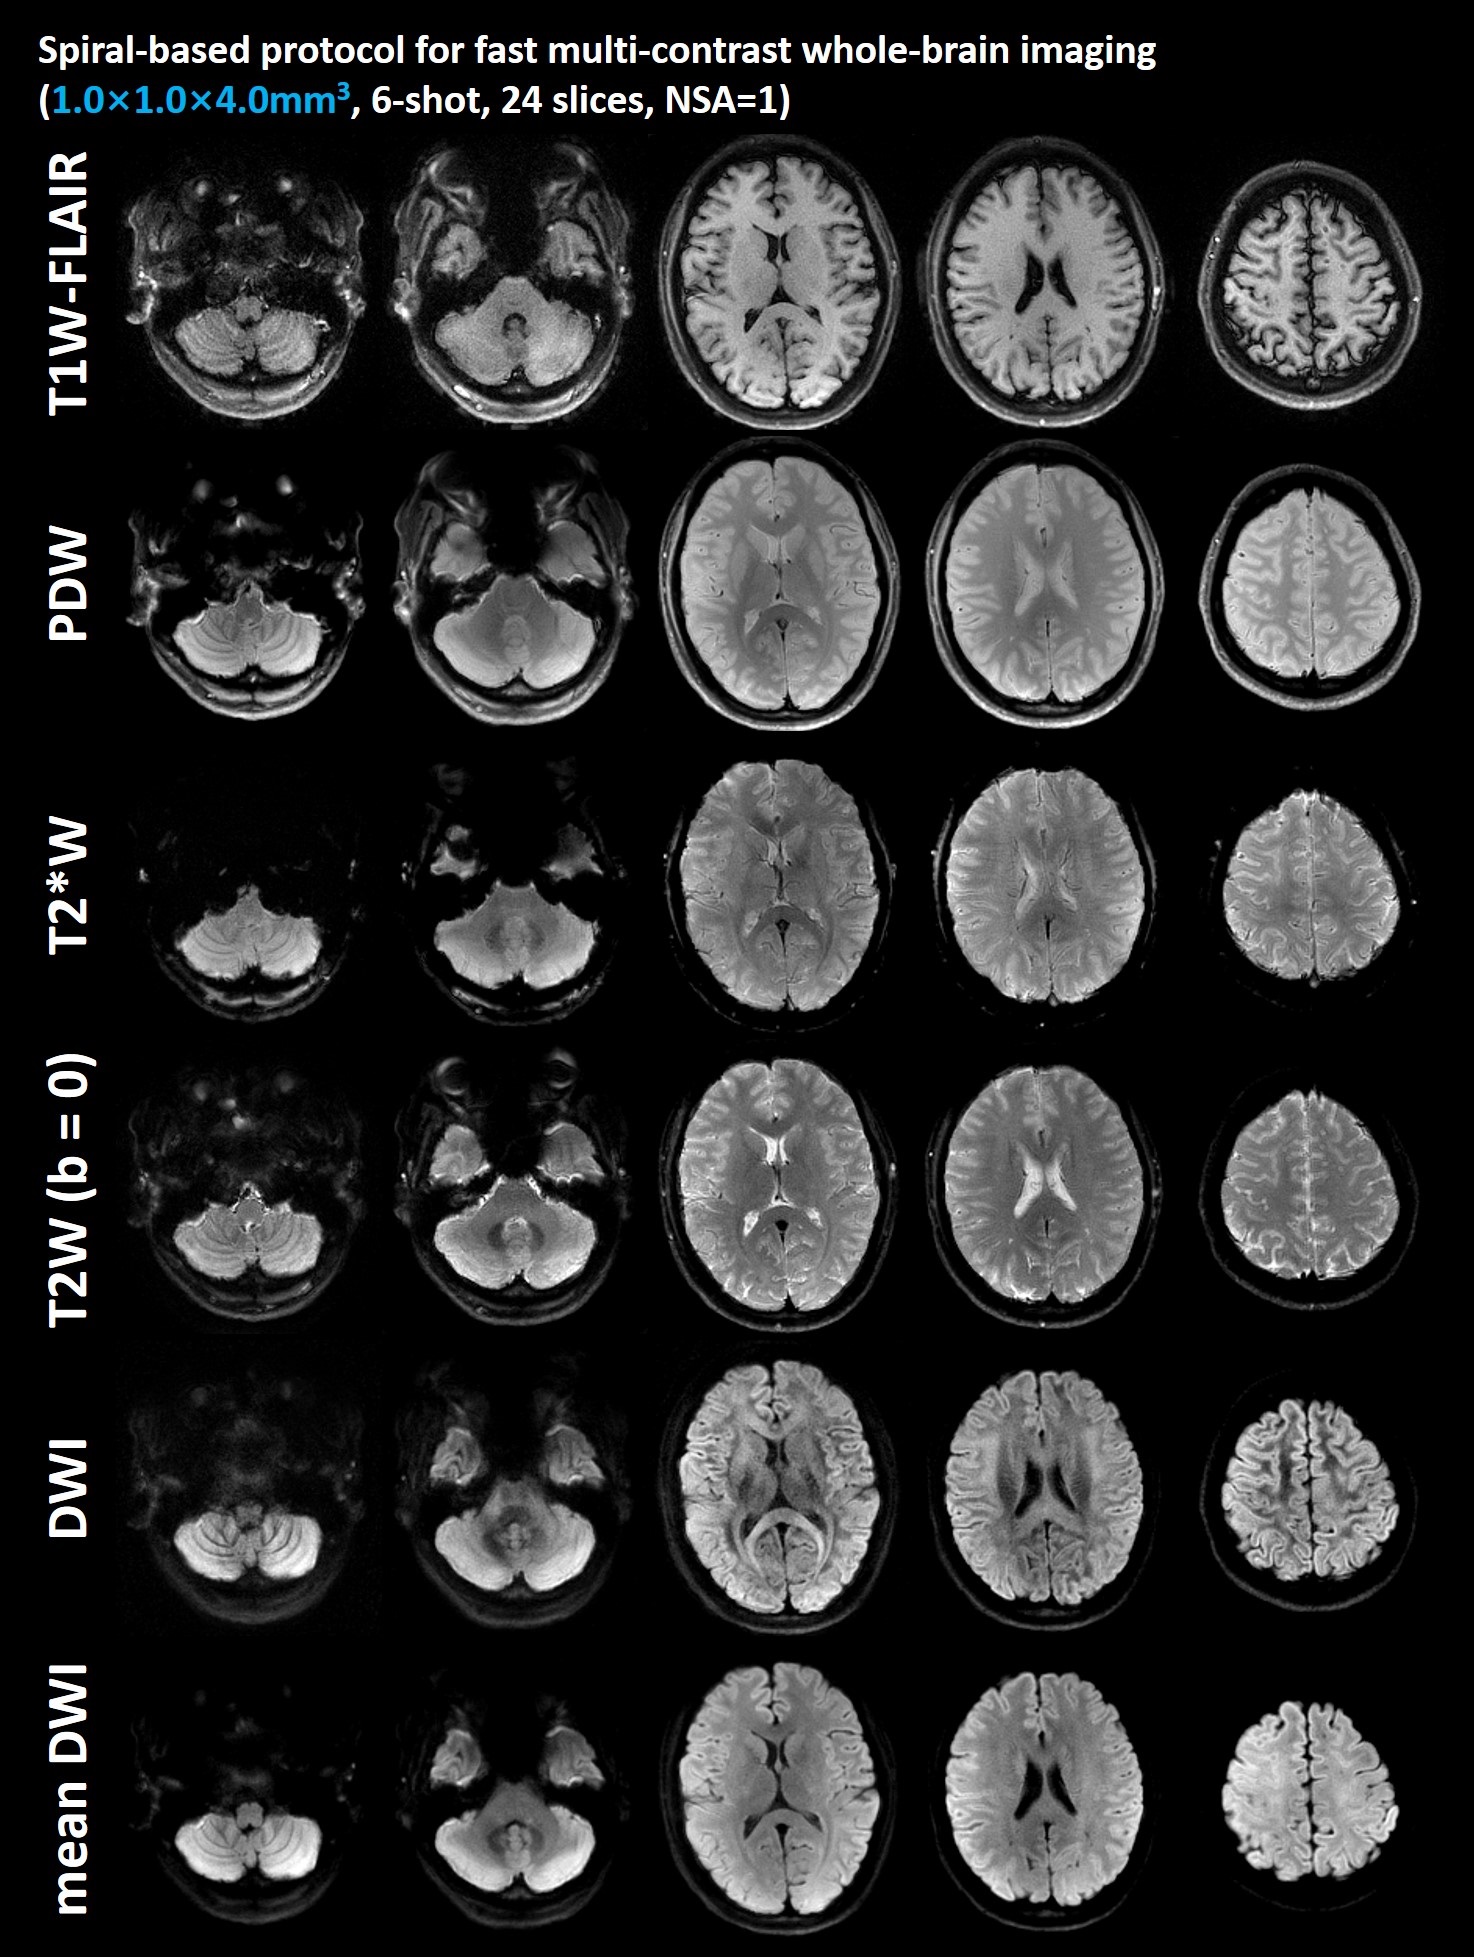

For Experiment 1, T1W-FLAIR, T2W, PDW, T2*W, DWI, mean DWI and ADC map from a slice of the healthy subject S1 are shown in the Figure 3. The total scan time of this 6-shot protocol is 128s.

Figure 3: T1W-FLAIR, T2W, PDW, T2*W, DWI, mean DWI and ADC map from a slice of the healthy subject S1. The scan time of each sequence is marked at the bottom of the image. The total scan time of this 6-shot protocol is 128s.